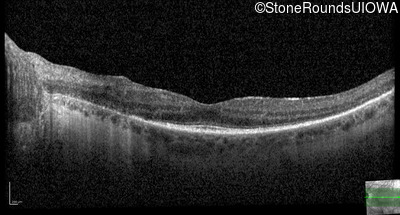

Optical Coherence Tomography - Left - 20/32

Exemplar / OCT Stack